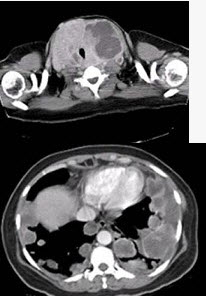

试题详情单项选择题青年女性,咽异物感1年,环状软骨左下方触及一直径2厘米的光滑结节,随吞咽上下活动,生长缓慢,颈部CT检查见下图,患者诊断最可能为()。 A、颈部淋巴瘤B、淋巴结转移癌C、甲状腺腺廇D、甲状舌骨囊肿E、颈淋巴结核正确答案:C答案解析:关注下方微信公众号,在线模考后查看热门试题开放性气管损伤的治疗措施包括()。对咽、食管闭合性损伤的治疗,正确的是()男性,40岁,颈部出现无痛性囊性包块2年颈部淋巴结结核多发生于()。开放性气管损伤所特有的临床表现是()。有助于颈淋巴结结核诊断的有()。颈外动脉的体表投影()。最有可能引起声嘶的疾病有()。颈部血管瘤的治疗不包括()。甲状舌管囊肿及瘘手术的治疗原则是()。颈动脉创伤性栓塞可出现()。颈部蜂窝织炎临床症状有()。颈部疼痛的原因一般不包括()。环磷酰胺()。颈浅部炎症不包括()。Ⅲ区()。胸导管()。某患者,左侧颈部胸锁乳突肌前缘及舌骨水平颈深上淋巴结在头颈肿瘤的诊断和治疗中具有颈部淋巴干()。